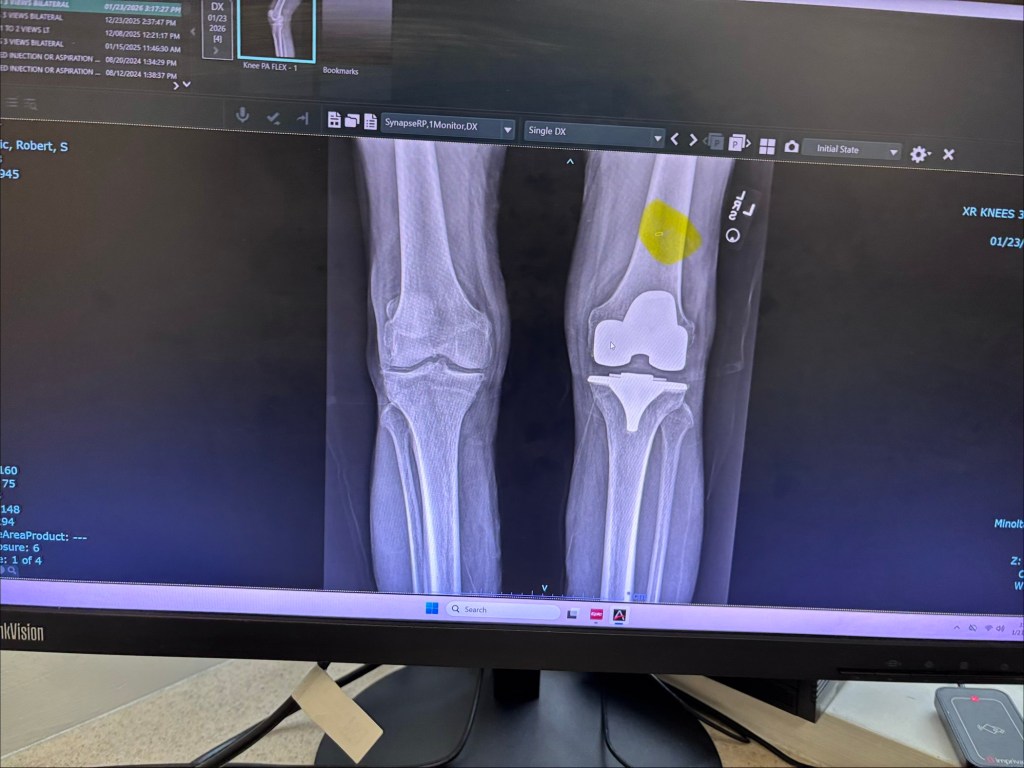

The week of January 18, 2026, I felt a sharp pain when I touched a spot above the knee and the surgical incision. Immediately, I suspected another forgotten staple. So I requested and appointment with my surgeon, Dr Moussa, and another X-ray of the knee.

This was done on January 23, 2026. And Dr Moussa confirmed that there is indeed another forgotten staple (highlighted on this X-ray shot).

He also issued and posted a PDF of his radiological diagnosis at the HonorHealth website.

Views: Bilateral knees, multiple views.

Impression/findings: Right knee tricompartmental osteoarthritis. Left knee arthroplasty in good position without evidence of loosening or fracture. There is a single retained staple cephalad area of the incision noted on radiographs.

Frank W Moussa, MD

Signed By: Frank W Moussa, MD on 1/23/2026 5:10 PM